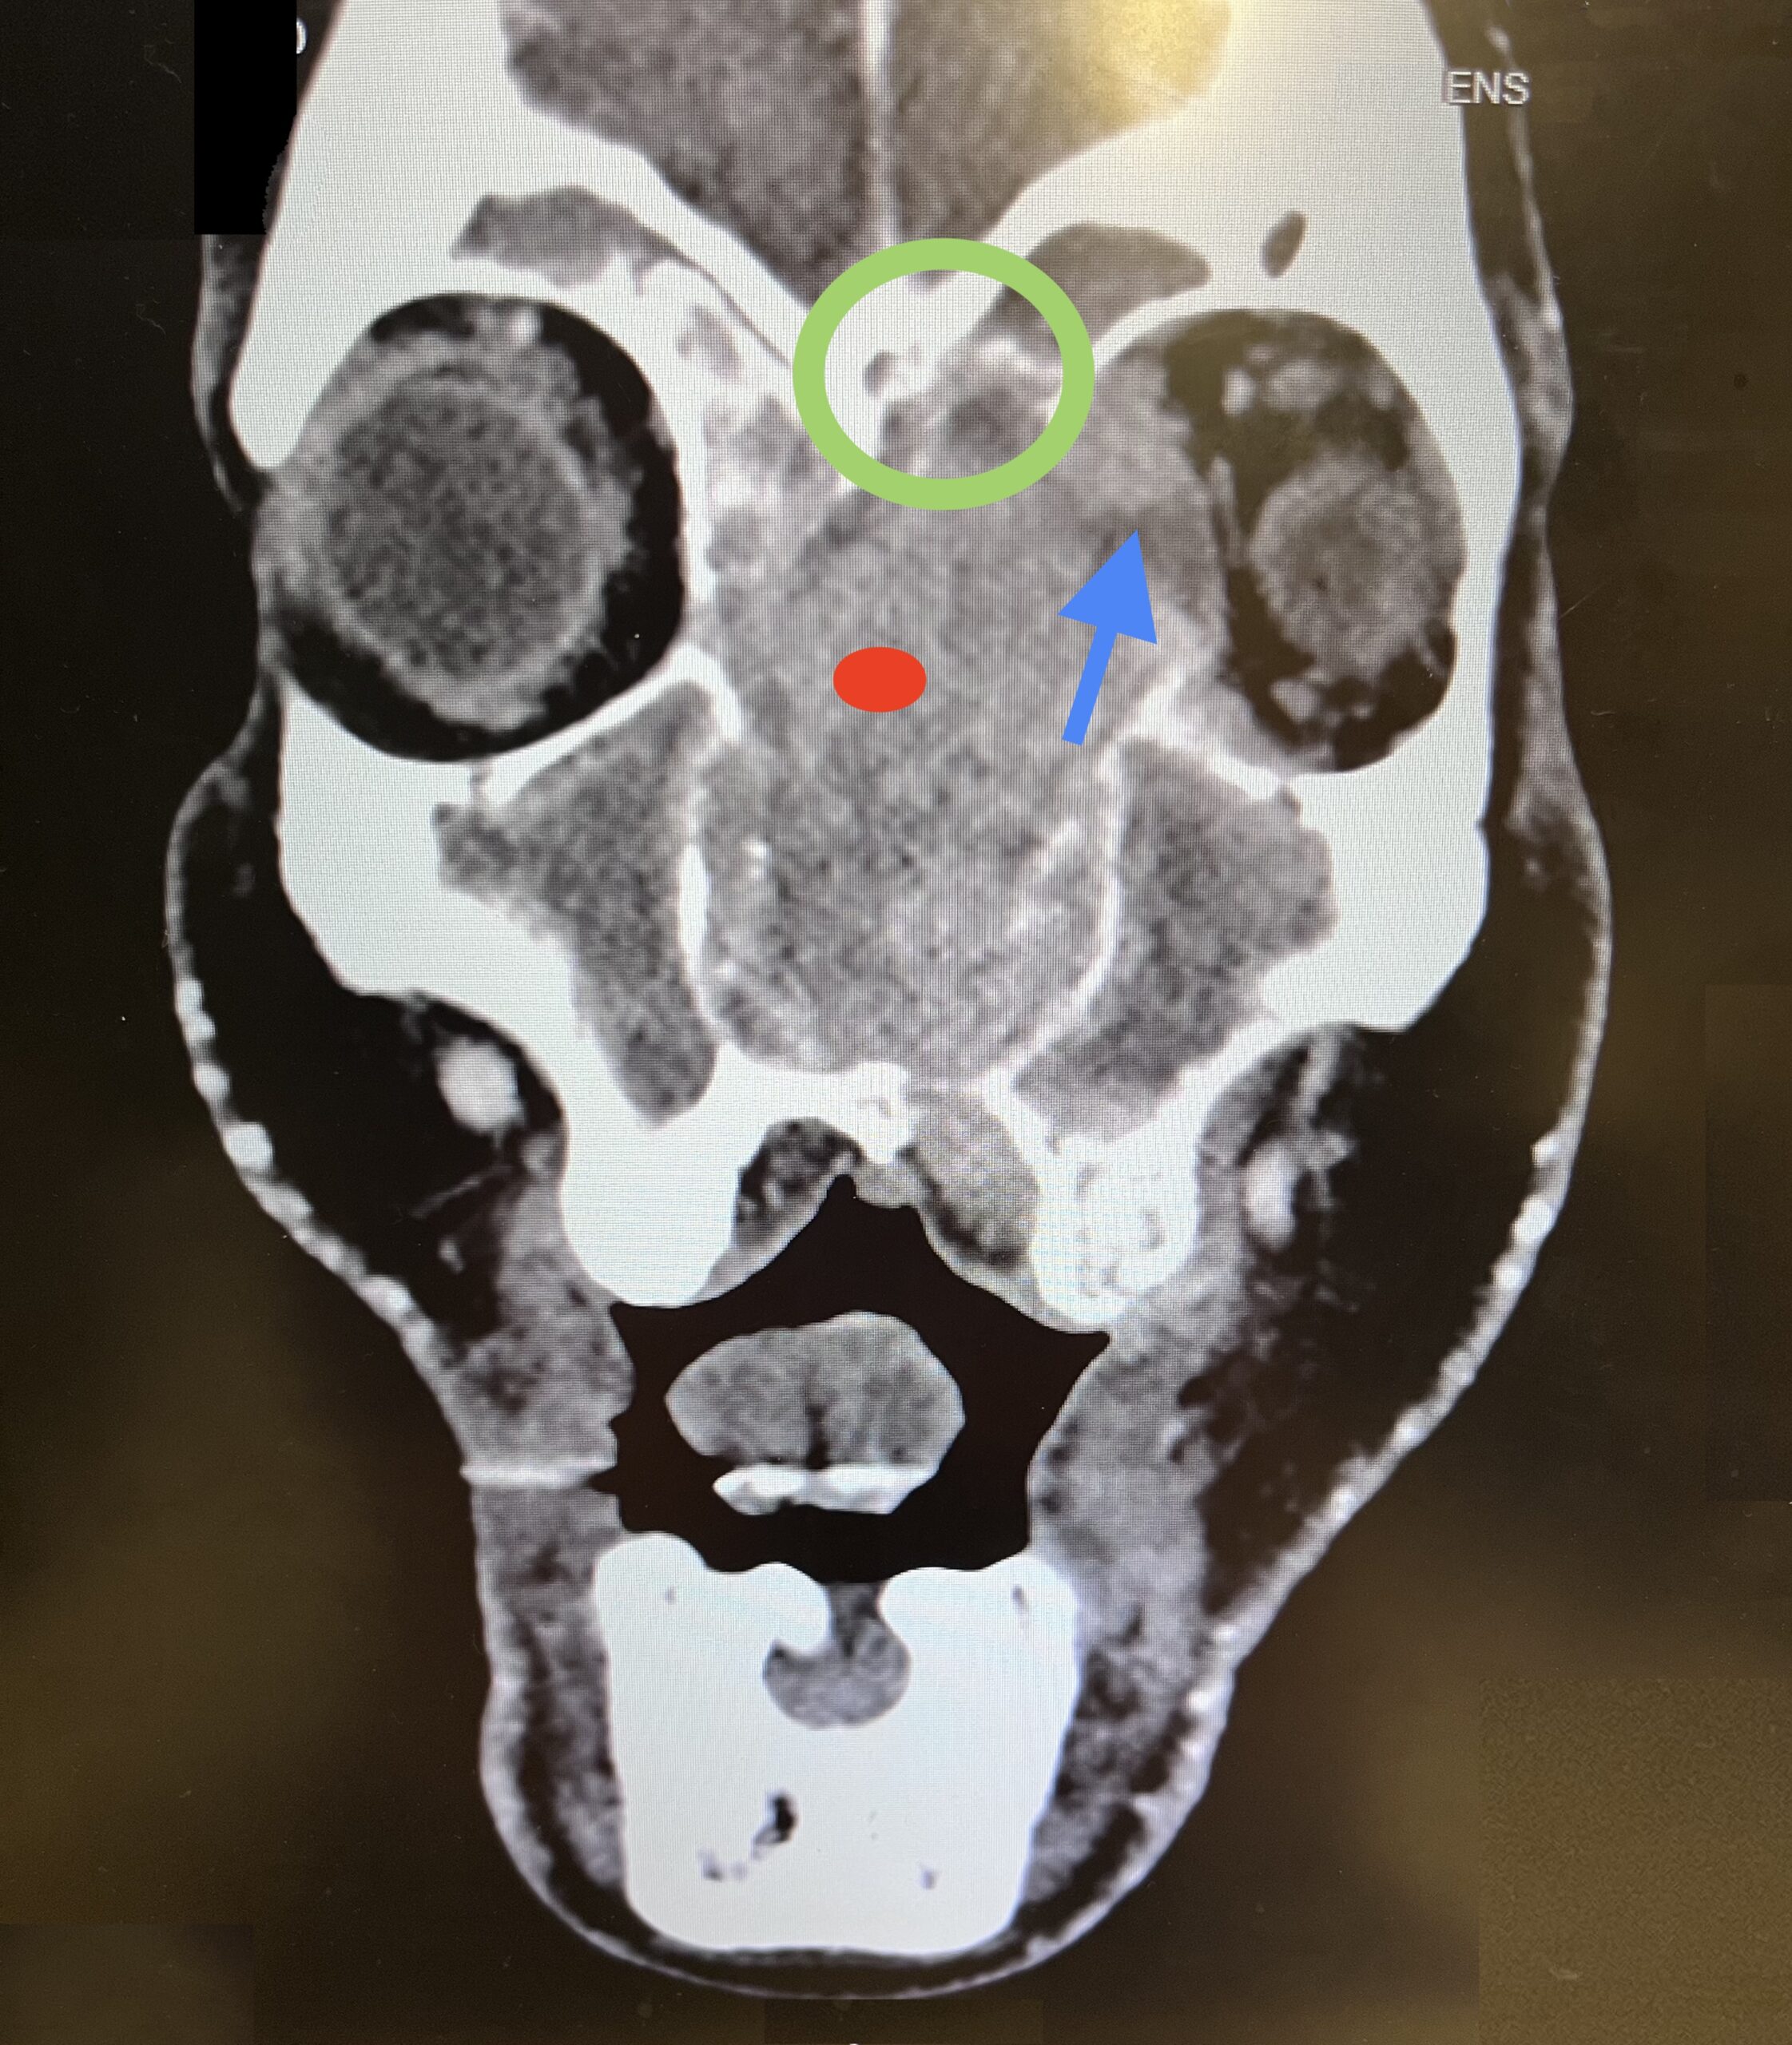

Sinonasal carcinoma is a rare malignancy that often presents with nonspecific symptoms, making early diagnosis challenging. Delayed recognition can lead to disease progression and worse outcomes. This case report emphasizes the importance of early identification, prompt imaging, and multidisciplinary management. A 73-year-old male with a history of anemia and hypertension presented with progressive facial swelling, 20-pound weight loss, and vision loss in the left eye over two months. Initially misdiagnosed with bacterial sinusitis, his symptoms persisted. Examination revealed a proptotic left eye and a large obstructive nasal mass. Computed tomography (CT) and MRI (magnetic resonance imaging) demonstrated a destructive sinonasal mass with skull base and intracranial extension. A biopsy confirmed sinonasal carcinoma, and the patient was started on chemoradiation therapy due to the inoperability of the tumor.

This case underscores the importance of recognizing red flag symptoms such as persistent facial swelling and neurological deficits. Multimodal imaging played a critical role in diagnosis. The literature suggests sinonasal carcinoma is often diagnosed late, reinforcing the need for early suspicion and specialist referral. Sinonasal carcinoma should be considered in patients with persistent facial or nasal symptoms. Timely imaging, biopsy, and interdisciplinary care are essential for optimizing outcomes.